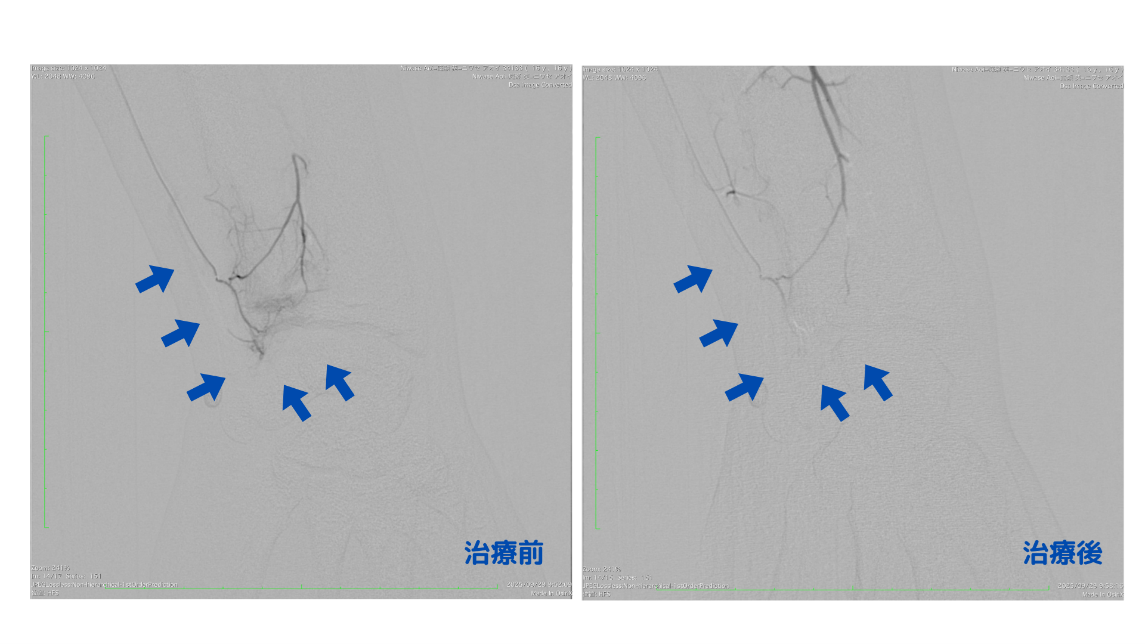

治療では、手首付近の動脈(尺骨動脈および骨間動脈)からカテーテルを通じ、患部に薬剤を投与しました。血管造影を行ったところ、炎症部位に異常な血管が増えていることが確認され、薬剤を流した際には普段の痛みが再現される「再現痛」がはっきりと認められました。これは、治療箇所が痛みの原因そのものであることを示しています。